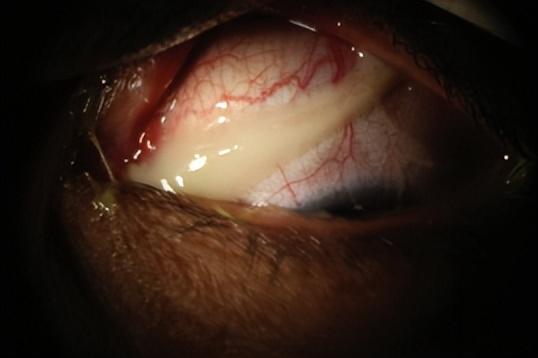

图1. 菌性结膜炎患者的眼部出现浓稠的分泌物